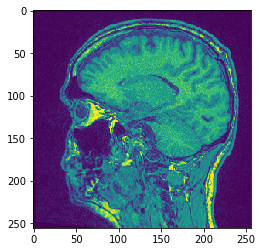

# Proyección Y Media

projection = cle.mean_y_projection(input_image)

# mostrar resultado

cle.imshow(projection)

../_images/651b6c99f2ac893b51f41872b1e6fbb4d58e1b34b378fd3f483faadd2f67d2ae.png